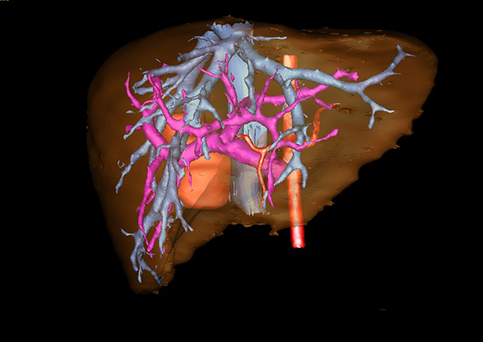

目前常用的检查方法有B超检查、CT、MRI、血管造影等。与其它的腹部肿块的诊断不同,对于小儿肝母细胞瘤血管造影具有重要的意义,可以作为手术前介入治疗的手段,也可为手术提供非常有效的影像学指导,但技术要求高,操作较复杂,且给患儿带来一定的痛苦。近年借助计算机辅助手术系统进行CT原始影像三维重建、手术规划和计算机虚拟手术技术,为精准肝脏手术提供了极为有效的技术支持。

近年来由于数字医学的发展,基于可视化三维重建技术的计算机辅助手术系统极大推进了小儿肝脏肿瘤的精准手术的进步。可以立体透视肝脏解剖、精确掌握肝段的边界、精确测算肝段乃至任意血管所支配的功能体积、准确定位病灶及其与邻近血管的解剖关系,最终对不同手术方案进行比较、筛选和优化。因此,计算机辅助手术规划系统是实现精准肝切除的有力辅助工具,是未来数字外科、精准外科等21世纪外科新理念的重要技术支撑。

计算机辅助手术规划系统具有良好的操作可行性、计算准确性和三维显示效果,可半透明、交互式显示真实的肝内立体解剖关系和空间管道变异,准确计算肝内管道的直径、走行角度,两点间的垂直距离,和任意血管的支配或引流范围等传统二维影像无法获取的信息,有助于实施个体化手术,提高了手术的确定性、预见性和可控性。计算机辅助手术规划系统可直观显示预留肝脏的结构和功能,并可通过虚拟切割功能辅助术者对手术方案进行蹄选和优化,系统评估手术风险和制定对策,改变了部分二维规划的术式和切除范围,使部分二维规划认为不能切除的患者成功手术,提高了手术的根治性、安全性和病变的可切除性,更加符合精准肝脏外科的术前规划要求。详见第11章。

随着计算机技术及影像检查技术的不断发展,以精确的术前影像学和功能评估、精细的手术操作为核心的精准肝切除技术日益受到重视。基于数字医学的计算机辅助手术技术(computer-assisted surgery,CAS)则是实现肝脏精准手术操作的基础。计算机辅助手术系统(CAS)可将术前二维(two dimensional,2D)的CT/MRI影像数据进行三维(three dimensional,3D)重建,建立个体化的肝脏三维解剖模型,清晰显示肝脏内脉管系统的走行及解剖关系,还原病灶与其周围脉管结构的立体解剖构象,准确地对病变进行定位、定性和评估,制定合理、定量的手术方案,实施个体化的肝脏血管取舍分配方案及实施精准肝脏手术。一般认为CAS包括:创建虚拟的患者的图像;患者图像的分析与深度处理;诊断、手术前规划、手术步骤的模拟;术中实时导航。应用本技术后,由于可以更清晰地看出肿瘤的界限,特别是根据肝血管的显影,判断出肿瘤与门静脉及肝静脉的关系以在手术前较准确地估计出手术成功切除的可行性。以往部分根据普通强化CT判断无法手术的病例而被评估为可以成功切除并手术成功。